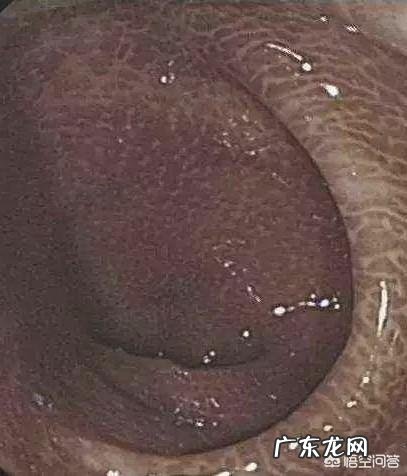

文章插图

“肠变黑”是一种以大肠粘膜色素沉着为特征的非炎性肠病,缺乏特异的临床表现,多在做肠镜时发现 。长期服用刺激性泻药,大黄、芦荟、番泻叶、决明子等蒽醌类中药属于刺激性泻药,损伤肠壁神经丛和粘膜细胞坏,进而影响正常的肠道蠕动和生理节律 。最终形成药物依赖,进一步加重便秘程度,同时坏死的粘膜细胞脱落或被吞噬,导致肠粘膜变黑 。对于肠已变黑的患者需立即停用蒽环类泻药,多可以恢复至正常颜色 。